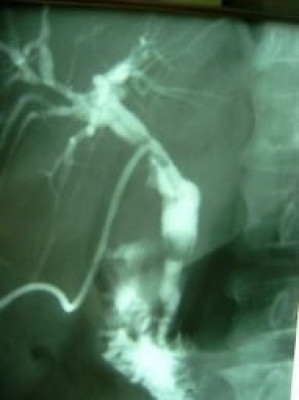

Extracción percutánea de cálculo de coledoco

Envíado por Dr. Carlos Miguel Zavaleta Consuegra